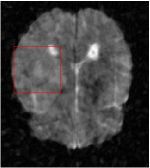

All the experiments are implemented on a Windows workstation with Intel Core i9 CPU at 3.3GHz and an Nvidia GTX-1080Ti GPU with 11GB of graphics card memory via TensorFlow Abadi et al. (2016). The parameters in the proposed network are initialized by using Xavier initialization Glorot and Bengio (2010). We trained the meta-learning network with four tasks synergistically associated with four different CS ratios: 10%, 20%, 30%, and 40%, and test the well-trained model on the testing dataset with the same masks of these four ratios. We have 300 training data for each CS ratio, which amount to total of 1200 images in the training dataset. The results for and MR reconstructions are shown in Tables 5.4 and 5.4 respectively. The associated reconstructed images are displayed in Figures 1 and 3. We also test the well-trained meta-learning model on unseen tasks with radio masks for skewed ratios: 15%, 25%, 35%, and random Cartesian masks with ratios 10%, 20%, 30% and 40%. The task-specific parameter for the unseen tasks are retrained for different masks with different sampling ratios individually with fixed task-invariant parameters . In this experiments, we only need to learn for three skewed CS ratios with radio mask and four regular CS ratios with Cartesian masks. The experimental training proceed on less data and iterations, where we performed on 100 MR images with 50 epochs. For example, for reconstructing MR images with CS ratio 15% radio mask, we fix the parameter and retrain the task-specific parameter on 100 raw data with 50 epochs, then test with renewed on our testing data set with raw measurement that sampled from radio mask with CS ratio 15%. The results associated with radio masks are shown in Table 5.4 and 5.4, Figure 2 and 4 for and images respectively. The results associated with Cartesian masks are list in Table 5.4 and reconstructed images are displayed in Figure 5.

Qualitative comparison between conventional and Meta-learning methods are shown in Figure 1 and 3, which display the reconstructed MR images of the same slice for T1 and T2 respectively, we label the zoomed-in details of HGG in the red boxes. We observe the evidence that conventional learning is more blurry and lost sharp edges, especially in lower CS ratios. From the point-wise error map, we find meta-learning has the ability to reduce noises especially in some detailed and complicated regions comparing to conventional learning.